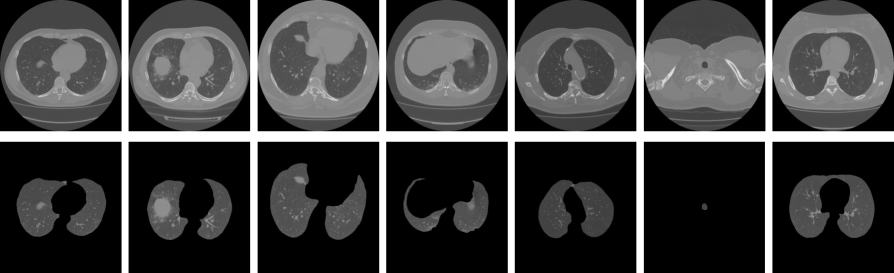

We extract five different 3D patches, named P1subscript𝑃1P_{1}, P2subscript𝑃2P_{2}, P3subscript𝑃3P_{3}, P4subscript𝑃4P_{4}, and P5subscript𝑃5P_{5}, having respective size of 16×16×91616916\times 16\times 9, 32×32×1232321232\times 32\times 12, 64×64×1564641564\times 64\times 15, 128×128×2012812820128\times 128\times 20, and 256×256×2725625627256\times 256\times 27. The original CT scans having size of 512×512×3651251236512\times 512\times 36 is named as P6subscript𝑃6P_{6}. The height and width of the patch P5subscript𝑃5P_{5} is half of the P6subscript𝑃6P_{6}, whereas these dimensions of the patch P4subscript𝑃4P_{4} is one-fourth of the P6subscript𝑃6P_{6}, and so on. We extract 2nsuperscript2𝑛2^{n} number of patches for a nthsuperscript𝑛𝑡n^{th}-time reduction of the height and width. Therefore, we train and test our network with 710407104071040, 355203552035520, 177601776017760, 888088808880, 444044404440, and 111011101110 samples for the 3D volumes P1subscript𝑃1P_{1} to P6subscript𝑃6P_{6}, respectively. The examples of the extracted patches are shown in Fig. 4, where we select the middle slices of the extracted patches of the same CT scan.

Refer to caption

Figure 4: Example of various extracted patches having different sizes, as mentioned earlier, where patches P1subscript𝑃1P_{1} to P6subscript𝑃6P_{6} are displayed in a) to f), respectively. The middle slices of each 3D patches are illustrated for the same sample (study_0258.nii.gz) in the MosMedData dataset. Slices are captured using a ITK-Snap windows version444http://www.itksnap.org/pmwiki/pmwiki.php?n=Downloads.SNAP3.

Different patches in Fig. 4 shows their respective resolutions, where it is seen that the patches P1subscript𝑃1P_{1} and P2subscript𝑃2P_{2} demonstrate very low resolutions. However, the effects of those patch resolutions are judged by classifying the NOR vs. NCP classes (see in subsection 2.1).

The well-defined segmentation, with less-coarseness, is an essential requirement for further identification. The incorporation of segmentation with the PRN further promotes the identification results than the PRN alone, as exposed in Table 4. Several examples of the segmented lung from our proposed unsupervised pipeline (as described in subsection 2.2) are depicted in Fig. 7 for qualitative evaluation.

(a)

Figure 7: Examples of lung segmentation results applying our unsupervised pipeline, as described in subsection 2.2.

However, the COVID-19 identification results incorporating lung segmentation with the PRN reflects its supremacy over the PRN alone, extending the weighted average type-II error by 1.4%percent1.41.4\,\% with respective improvements in average positive predictive value by 2.8%percent2.82.8\,\% (see in Table 4). The class-imbalanced identification is also dwindled due to segmented lung area utilization over the full CT volumes. The reasonable ground for those enhanced performances due to the segmentation is that it extracts an abstract region, enabling the classifier to learn only the precise lung areas’ features while avoiding the surrounding healthy tissues of the chest CT scans.